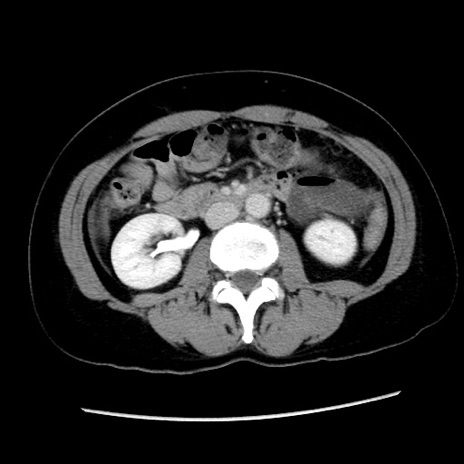

矢状断像

【症例】 50歳代女性

【主訴】 腹痛

【現病歴】前日生レバーを食べた。今朝に排便あり。 昼前に突然発症の腹痛を生じ、当院救急外来を受診した。

【既往歴】 子宮筋腫にてで子宮全摘後

【身体所見】 意識清明、腹部:平坦、軟、下腹部やや左を中心に圧痛・反跳痛あり、筋性防御あり

【データ】WBC 7800、CRP 0.07